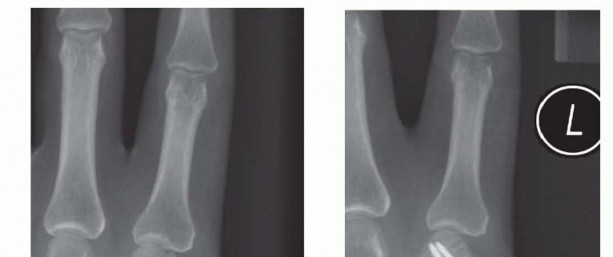

TECH FIG 3 • A. Second metacarpal fracture with an intact adjacent metacarpal and a narrow medullary canal. B. Fixation using one proximal pin to secure the shaft and two distal pins to secure the distal fragment. C,D. Fracture where the narrow medullary space made it difficult to pass a second wire through the canal. Supplemental fixation achieved through a transverse pin on the distal fragment. The fracture is anatomically reduced through closed means.The proximal fragment is first stabilized by pinning it to the adjacent intact metacarpal.Use the nick and spread technique while placing the wires to minimize the risk of iatrogenic cutaneous nerve injury.Keep pressure between the adjacent metacarpals to prevent convergence between the metacarpals as the wire is advanced.Be mindful of the arch-like arrangement of the metacarpals.The distal fragment is stabilized by placing two wires through the distal fragment into the adjacent intact metacarpal (TECH FIG 3B).The hand is immobilized in a forearm-based splint with the MP joints flexed 70 to 90 degrees while the pins are in place. The pins are kept for 3 to 4 weeks. The IP joints are left free to move.The pins are removed at 3 to 4 weeks, and the hand is placed in a removable splint for an additional 2 weeks.Alternatively, transverse pins can be used to augment other forms of fixation or control rotation (TECH FIG 3C,D).1. Open Reduction and Plate/Screw Stabilization of Metacarpal Fractures